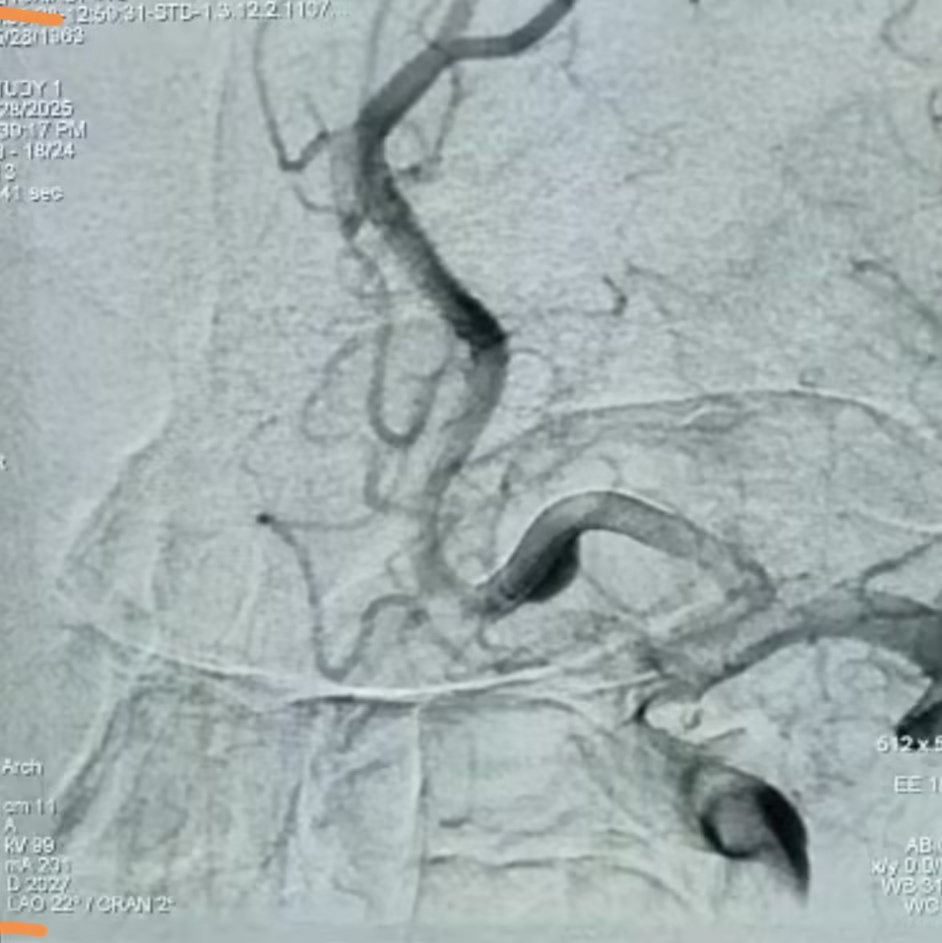

动脉瘤术后

手术过程中,医疗团队精准释放2.5mm×18mm血流导向密网支架,完全覆盖动脉瘤颈。术中即刻造影显示动脉瘤瘤腔内造影剂滞留,载瘤动脉及邻近血管通畅无狭窄,手术成功。